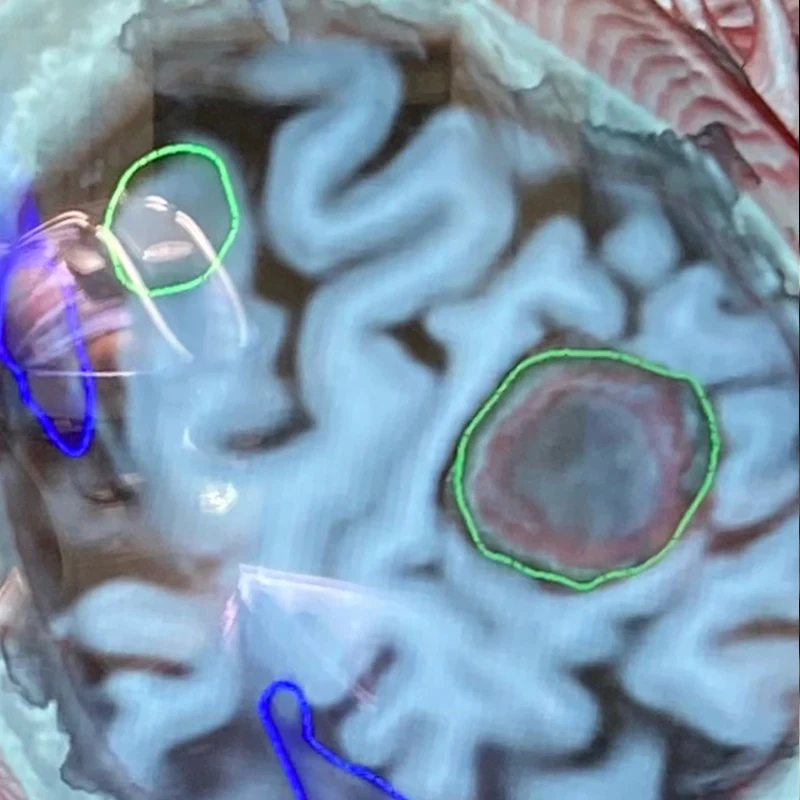

Figure 1. This composite figure illustrates intraoperative mapping of primary somatosensory cortex at high resolution using 2,048 surface microelectrodes.

Middle Center. Oblique cross-section through the T1-weighted MRI highlighting the tumor, green, right, compressing the postcentral (sensory) gyrus.